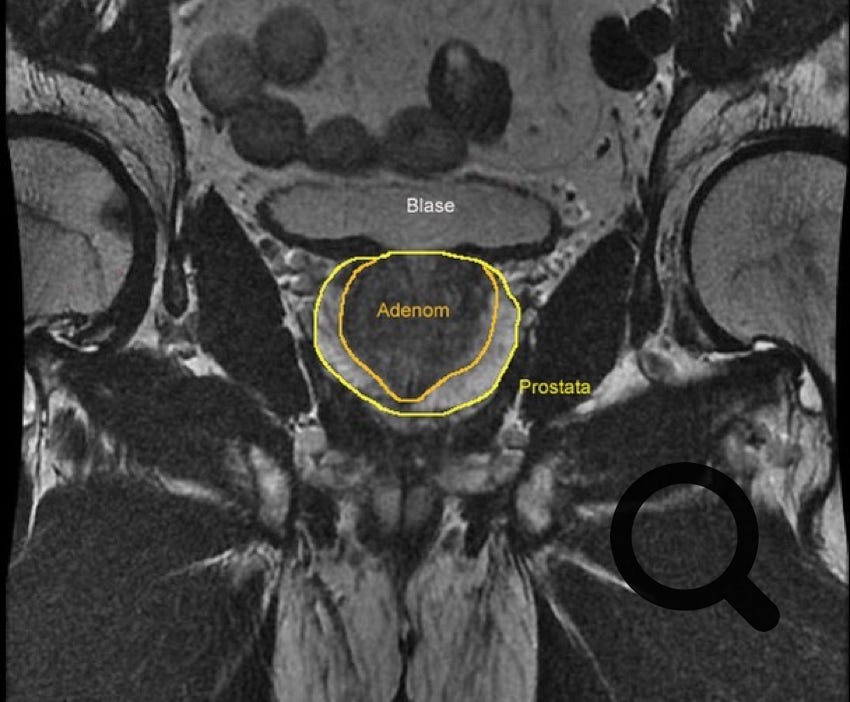

BPH steht für benigne Prostatahyperplasie. Damit ist die gutartige Prostatavergrößerung gemeint, welche mit zunehmenden Alter in individuell unterschiedlichem Umfang entsteht. Von einer normalen Größe von 15-25 ml kann die Prostata im Laufe der Zeit dadurch eine durchaus stattliche Größe annehmen. Diese gutartige Wucherung (auch 'Adenom' genannt) entsteht um die Harnröhre, welche durch die Prostatadrüse verläuft und verdrängt das eigentliche Prostatagewebe am Rande der Prostatadrüse. Dieses ist auf einer Kernspintomographie (MRT-Bild unten) sehr gut zu erkennen. Die Prostata liegt unterhalb der Harnblase und ist hier gelb umrandet; das dunklere Areal innerhalb der Prostata zeigt die gutartige Vergrößerung, welche das heller dargestellte eigentliche Prostatagewebe als dünnere Schale am Rande verdrängt. Durch diese Vergrößerung wird die Prostata in der Regel weniger elastisch und verhindert auf diese Art eine normale zügige Blasenentleerung: der Harnstrahl wird schwächer. Die Harnblase kann unterschiedlich reagieren. In der Regel wird die Harnblase kräftiger und entwickelt eine muskelstarke Wandung. Dadurch wird die Harnblase leider auch weniger dehnbar und das Fassungsvermögen wird zunehmend kleiner. Ausserdem reagiert die Blase dann irgendwann heftiger bei kleineren Füllmengen: der Harndrang wird zwanghaft, sowohl tagsüber als auch nachts. Im Extremfall ist die Blasenentleerung dann kaum noch gut zu kontrollieren. In anderen Fällen resigniert die Harnblase und bringt nicht mehr die Kraft auf, die für eine vollständige Entleerung erforderlich ist: es entsteht Restharnbildung. In seltenen Fällen staut der Urin dann (schleichender Prozess und deshalb häufig unbemerkt !) bis in die Nieren zurück: dann droht ein Nierenversagen. Irgendwann kann die Situation dazu führen, dass die Harnblase nicht mehr entleert werden kann: es kommt zum Harnverhalt. Letzteres ist in der Regel ein schmerzhaftes Ereignis mit prall gefüllter Blase und starkem Harndrang. Häufig wird ein Harnverhalt durch eine vermehrte Füssigkeitseinnahme oder Alkoholgenuss ausgelöst. In seltenen Fällen hat sich fast unbemerkt immer mehr Resturin gebildet und die Harnblase läuft dann zum Schluss über, wobei sich dann ständig unkontrolliert tropfenweise Urin entleert ('Überlaufblase').

BPH im MRT